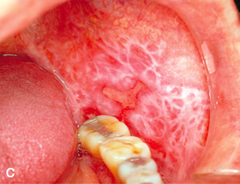

benign tumor of epithelium; pedunculated; cauliflower like appearance; found mostly on palatal area/uvula

Front

Papilloma